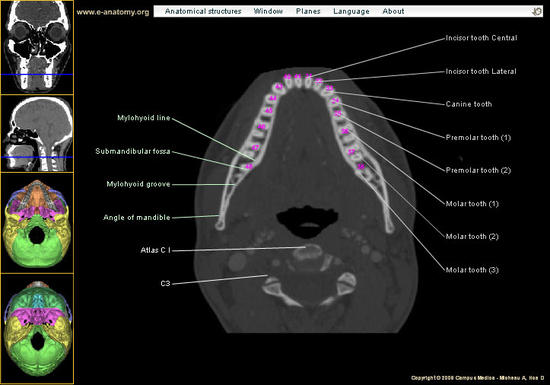

معرفی يه سايت خوب و جالب براي يادگيري Brain CT (نرمال و غیرنرمال)

Introduction To Head CT

تصاویر يك Brain CT نرمال

Head CT Anatomy